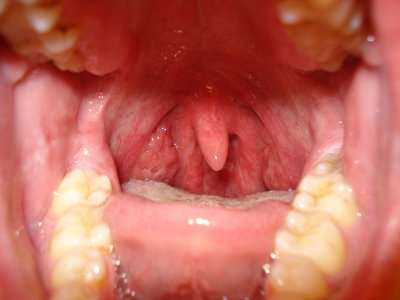

вот пара снимком от 2006 года и пара снимков сегодняшних... надоело оно мне (горло) вот и пишу, может есть решение проблемы.....

так вот, лет с 10-15 назад хорошенько простыл, болело горло и т.д. (стандартные симптомы), но после этого постепенно стали появляться язвы на миндалинах, которые всё это время только прогрессировали и сейчас, когда простываю, они начинают как бы гнить и обростают (наверно) гнойниками (достаточно твёрдые на ощупь, если достать от туда) и пахнут крайне зловонно, когда вроде здоров гнойники исчезают, НО остаются уже сквозные дырки в которые забивается пища и тоже гниёт и пахнет! когда сильно это надоедает начинаю чистку, просто беру тонкую палочку с ваткой и каждую дырку в миндалинах прочищаю, весь мусор из дырок удаляю и после этого миндалины вроде как даже здоровее становятся и запах пропадает!

вопрос специалистам вот в чём: как эти дырки заживить, чтобы в них заново не образовывались гнойники и чтобы в них не попадала пища?